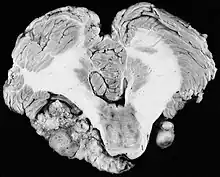

There have been cases of tumors that were actually asymptomatic until very large and at a critical stage. Tumor growth rates are highly variable: some small VSs (perhaps 50%) do not grow at all; some few grow for a time and then shrink; some appear dormant but suddenly grow rapidly. In general, although studies differ, VSs that grow are slow-growing at an average rate of 1.2 to 1.9 mm per year. IAC tumors that grow beyond 1.5 cm in diameter expand into the relatively empty space of the cerebellopontine angle, taking on the characteristic 'ice-cream-cone' appearance seen on MRIs. As 'space-occupying-lesions,' the tumors can reach 3 to 4 cm or more in size and infringe on the facial nerve (facial expression) and trigeminal nerve (facial sensation). Advanced hearing loss and spells of true vertigo may occur. Very large tumors are life-threatening when they press on the cerebellum or cause brainstem compression. Late symptoms of very large VS include headache, nausea, vomiting, sleepiness, mental confusion and eventually coma.[3][4]